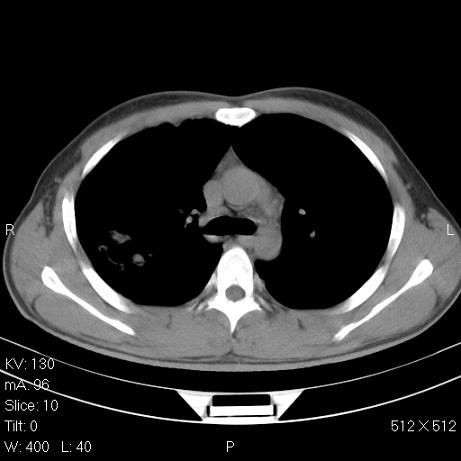

标题: CT7171B:补充治疗后2周复查 [打印本页]

标题: CT7171B:补充治疗后2周复查

治疗后2周复查,请讨论

结合以前的ct片,还是考虑肺挫伤,吸收多了。

支持:创伤性湿肺。现肺挫裂伤(出血 积气)大部分吸收。建议继续治疗!

结合以前的ct片,支持创伤性湿肺。现大部分吸收。

支持:创伤性湿肺、肺挫裂伤。现肺挫裂伤(出血、渗出、液气腔)大部分吸收。建议继续治疗!

支持:创伤性湿肺、肺挫裂伤。现肺挫裂伤(出血、渗出、液气腔)大部分吸收.

结合老片支持创伤性湿肺、肺挫裂伤。

经治疗后病灶明显吸收,考虑创伤性湿肺、肺挫裂伤